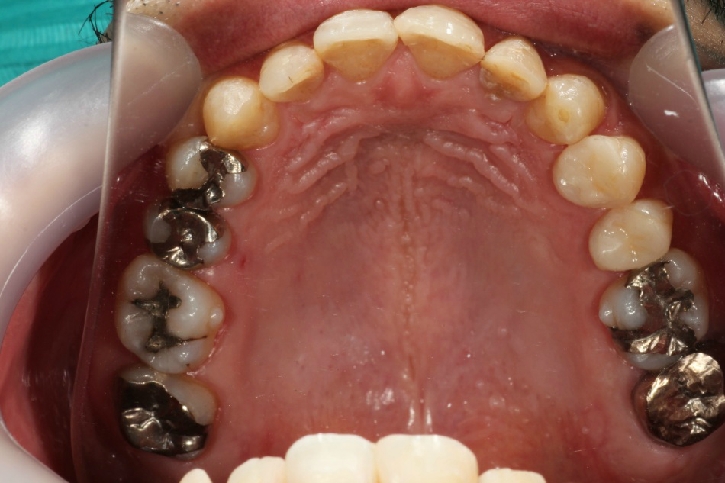

オールセラミックス修復

担当歯科医師:丸林浩太郎

2013年5月11日千葉市中央区 K.N様 上顎12番 オールセラミッククラウン修復